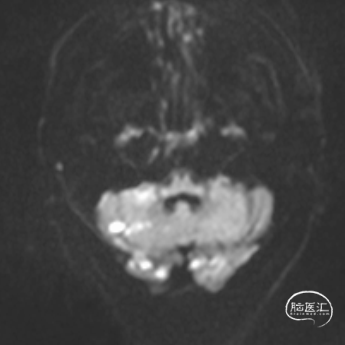

1.急查头颅MRI+RMA示:

2.右侧小脑半球、双侧枕叶、左侧颞叶脑梗塞;

3.桥脑区、双侧基底节区陈旧性脑梗塞;

4.脑白质脱髓鞘;

5.双侧椎-基底动脉、双侧大脑后动脉、右侧大脑前动脉闭塞;

6.右侧颈内动脉狭窄;

7.脑动脉硬化。

MRI

MRA